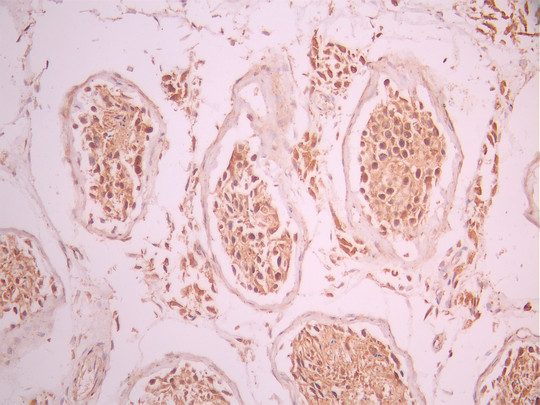

IHC image of CSB-RA990431A0HU diluted at 1:100 and staining in paraffin-embedded human testis tissue performed on a Leica BondTM system. After dewaxing and hydration, antigen retrieval was mediated by high pressure in a citrate buffer (pH 6.0). Section was blocked with 10% normal goat serum 30min at RT. Then primary antibody (1% BSA) was incubated at 4°C overnight. The primary is detected by a Goat anti-rabbit polymer IgG labeled by HRP and visualized using 0.05% DAB.